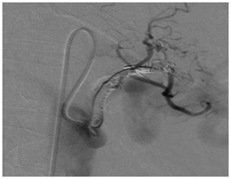

In Aug 2012 he represented and a repeat CT scan showed recurrence of pseudo-aneurysm close to the lesser curve of stomach and distal body/tail of pancreas. Angiogram showed that the pseudo-aneurysm had repurfused despite previous coils in left gastric artery and the left gastric artery was then again satisfactorily re-occluded (Figure 1).

Figure 1 CT guided embolization of the left gastric artery.